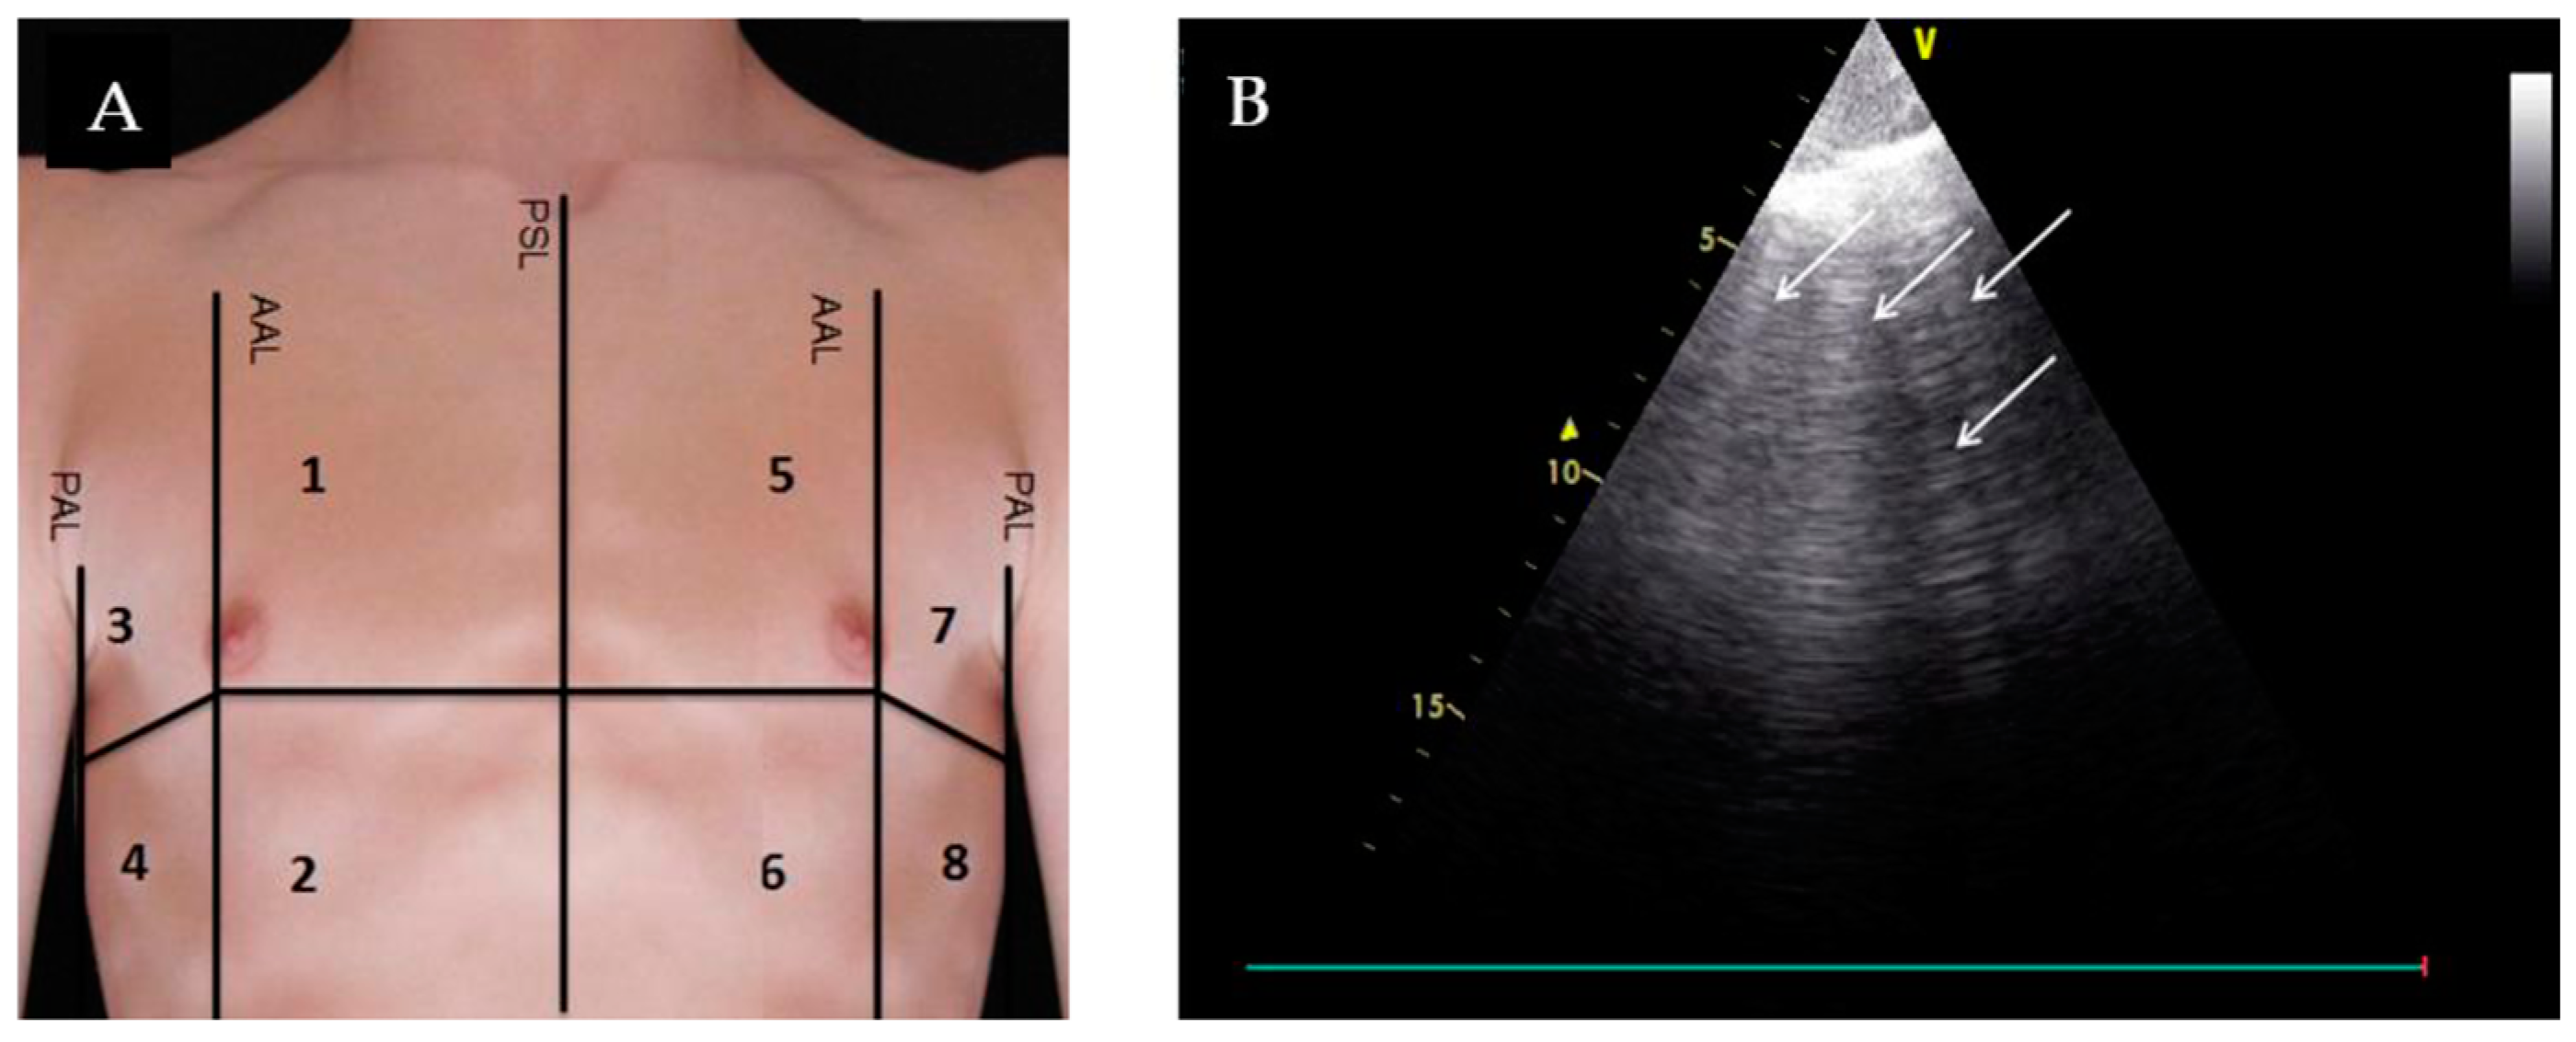

3. Lung Ultrasound (LUS)

| Lung Ultrasound | ||||

| Evaluation for B-lines | Absence of B-lines |

|

| |